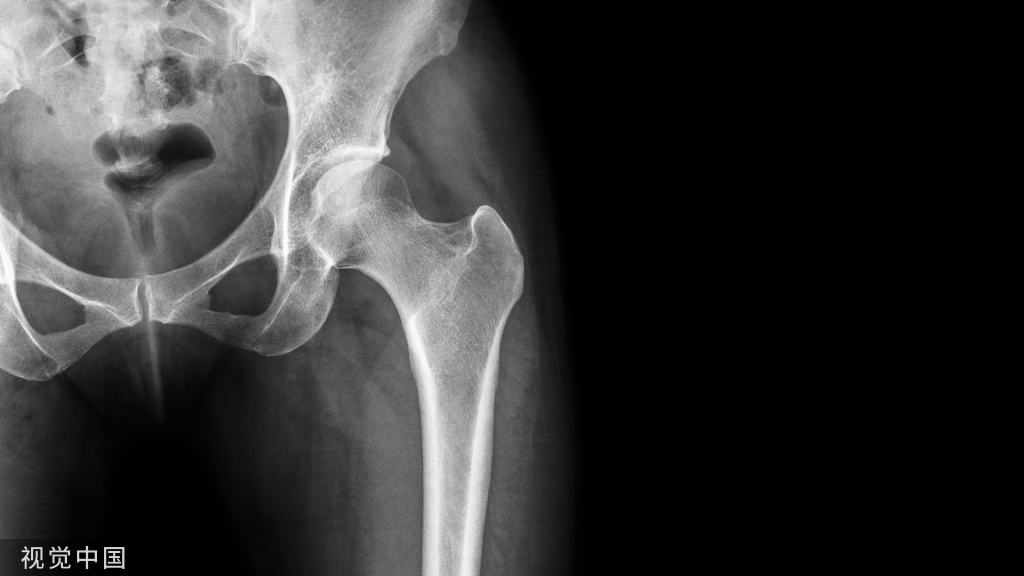

以下的内容介绍了臀大肌、臀中肌、臀小肌、梨状肌、下孖肌、上孖肌和闭孔内肌、闭孔外肌和股方肌的触诊。

髂嵴、股骨大转子和坐骨结节是臀区最基本的骨性标志。臀襞儿近水平位,大致与臀大肌下缘相一致、稍斜向下外侧。